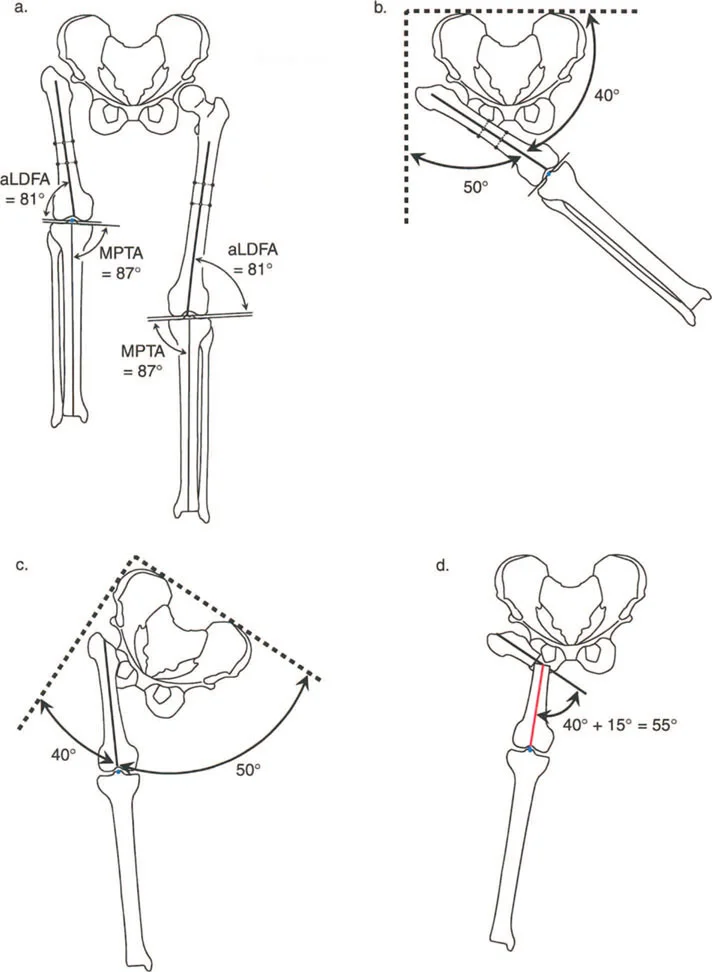

- الزاوية الفخذية البعيدة الجانبية الميكانيكية (mLDFA): الطبيعي حوالي 87 درجة.

- الزاوية الظنبوبية القريبة الإنسية (MPTA): الطبيعي حوالي 87 درجة.

- الزاوية الظنبوبية البعيدة الجانبية (LDTA): الطبيعي حوالي 89 درجة.

- عندما تكون إحدى هذه الزوايا غير طبيعية، فإنها تشير إلى موقع التشوه (في الفخذ، الساق، أو داخل المفصل).

الشكل 12-29أ، ب: الاختلافات في القياسات الإسقاطية الناتجة عن منظورين مرجعيين مختلفين (المتطابقات المنظرية). في المنظر الأمامي الخلفي بالنسبة للقطعة المرجعية الأمامية للركبة، تبدو الساق بـ 4.75 درجة من التقوس للداخل. أما بالنسبة للقطعة المرجعية الأمامية للقدم، فتبدو بـ 5.5 درجة من التقوس للخارج. تختلف قياسات الدوران أيضًا بناءً على منظور المراقب.

- يعتمد تحليل التشوه بشكل كبير على زوايا توجيه المفاصل القياسية لتحديد ما إذا كان التشوه في عظم الفخذ، أو الساق، أو داخل المفصل نفسه. تشمل الزوايا الرئيسية:

- الزاوية الفخذية البعيدة الجانبية الميكانيكية (mLDFA): الطبيعي 87 درجة.

- الزاوية الظنبوبية القريبة الإنسية (MPTA): الطبيعي 87 درجة.

- الزاوية الظنبوبية البعيدة الجانبية (LDTA): الطبيعي 89 درجة.

- عند إدخال البيانات في برنامج CAD الخاص بالمحاور الستة، فإن التعرف على أي من هذه الزوايا غير طبيعي يحدد الجزء المرجعي والمعايير الدقيقة للتصحيح المطلوب.